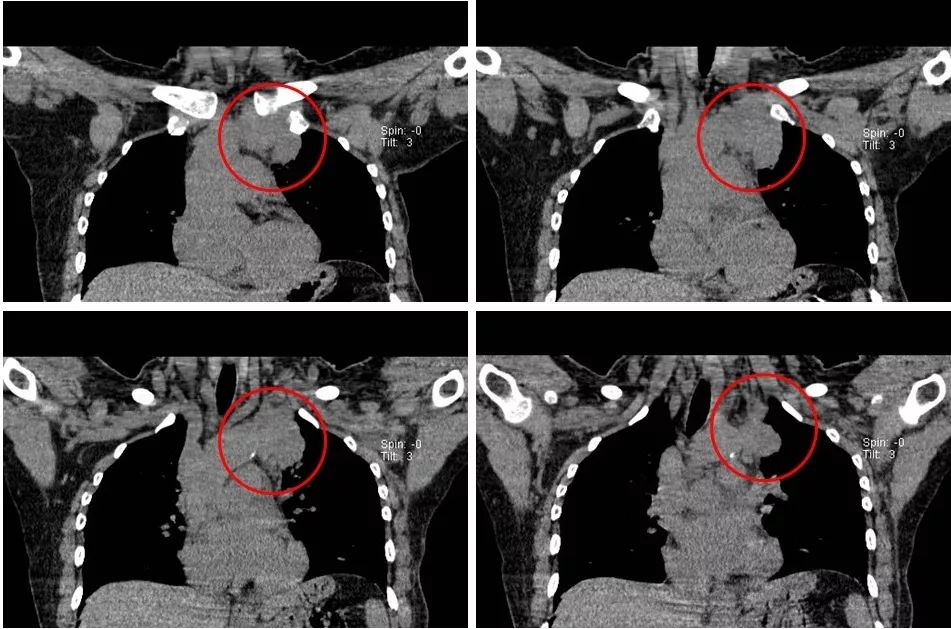

接受TC(卡铂)+曲妥珠单抗单周方案治疗。治疗2个周期后复查:淋巴结彩超示:左锁骨上淋巴结缩小,大的0.6×0.4cm;复查胸部CT示:左侧纵隔肿物缩小,最大截面约6.0×2.9cm。治疗4个周期后再次复查,淋巴结彩超示:左锁骨上淋巴结缩小,大的0.6×0.4cm;复查胸部CT示:左侧纵隔肿物缩小,最大截面约3.1×2.4cm。治疗6个周期后再次复查,淋巴结彩超示:左锁骨上淋巴结缩小,大的0.3×0.3cm;复查胸部CT示:纵膈肿物缩小明显,病灶局部包绕头臂静脉,与胸壁边界不清。评价治疗有效,继续行TC(卡铂)方案化疗+靶向治疗。治疗8周期后再次胸部CT示:纵隔肿瘤缩小明显,最大截面由最初的7.2×2.9cm缩小为2.7×2.9cm,评价为PR。8周期治疗后,患者出现腹泻,大便次数8-10次/天,水样便,影响日常生活,根据NCI分级属3级重度腹泻。10天左右缓解;II度骨髓抑制。患者拒绝继续化疗,曲妥珠单抗改为21天/周期。

图2. 治疗2周期后复查胸部CT平扫

图3. 治疗4周期后复查胸部CT平扫

图4. 治疗6周期后复查胸部CT平扫